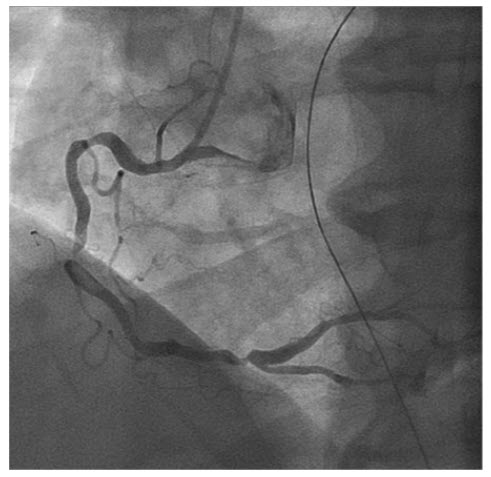

A 37-year-old man known for obesity felt typical chest pain while playing tennis accompanied by nausea, dyspnea, and sudations. The ECG shows STsegment elevation. He is immediately admitted to the catheterization laboratory (Fig. below).

What is the underlying pathology?

Thrombotic occlusion of the left main trunk. The coronary angiography shows thrombotic occlusion of the left main trunk artery. This lesion has been treated with thromboaspiration and implantation of a DES.